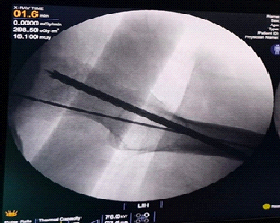

Subsequent attempts to free the broken tip using a thicker guidewire inadvertently pushed it further toward the joint cavity. Eventually, it was visualized to be lodged in the acetabulum on fluoroscopy. To retrieve the broken wire, the remaining part of the guidewire was aligned with the broken tip (Fig. 2) over which a dynamic hip screw inner reamer was gently hand-reamed (Fig. 3). This made sure the reaming did not create another tract. This maneuver facilitated mobilization of the wire but also pushed it further (Fig. 4). Finally, using an arthroscopic grasper under continuous fluoroscopic guidance, the fragment was successfully retrieved (Fig. 5).

Figure 2: Broken guide wire aligned with the broken tip before trying to over-ream.